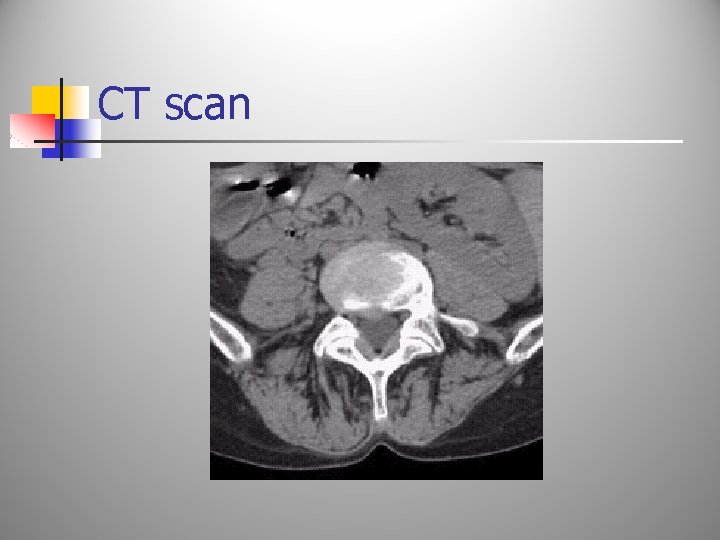

Diagnostics: Discogram n n n Test use: This test is used to identify whether an intervertebral disc is the source of the patient’s low back pain. Procedure: a radio-opaque dye is introduced into the center of the vertebral disc. Results: If the patient’s pain is reproduced, then it is inferred that the intervertebral disc is the source of the pain. If the patient experiences pain that is different than the normal pain, then the disc is not responsible. This procedure is painful to the patient. A ct scan may also be performed to identify the integrity of the disc.

Diagnostics: Myelogram n n n Test use: To identify anatomical abnormalities within the spinal canal. Procedure: A radio-opaque dye is placed into the dural sac and a CT scan of the area is then performed. Results: The CT scan is then read to identify whether any filling defects are seen within the spinal cord and the nerve roots. Defects may represent, a herniated disc, bone spurs, infections, malignancies, etc.

CT scan